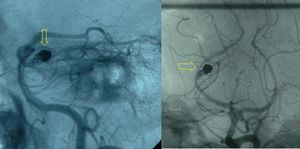

يتم الوصول للعضو المطلوب عن طريق سلوك التوجيه أو القساطر. وعلى حسب العضو، قد يكون الوصول له صعبًا للغاية ومستهلكًا للوقت. يتم تحديد وضع الشريان أو الوريد السليم الذي يغذي النسيج المرضي عن طريق تصوير الأوعية بالطرح الرقمي. يتم استخدام تلك الصور بعد ذلك كخريطة لطبيب الأشعة التدخلية للوصول إلى الوعاء الدموي الصحيح عن طريق استخدام قسطرة أو سلك مناسبـ بالاعتماد على 'الشكل' التشريحي المحيط.

بمجرد الوصول للمكان، يمكن أن يبدأ العلاج. تكون السدادة الصناعية المستخدمة عادة واحدة مما يلي:

بمجرد إدخال السدادة الصناعية بنجاح، يتم تصوير الأوعية بالطرح الرقمي مرة أخرى للتأكد من نجاح العملية.